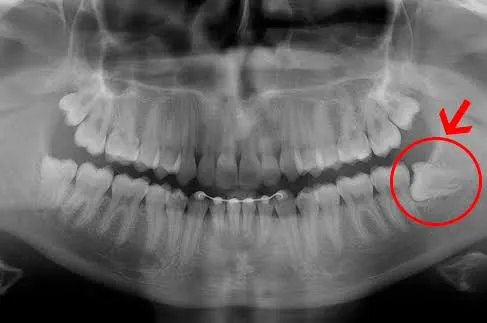

A Sorria 360 é uma clínica de referência em odontologia, especializada em Bucomaxilo, que oferece serviços essenciais para quem sofre com dor de dentes e problemas com siso. Com uma equipe altamente qualificada de profissionais, estamos preparados para realizar diagnósticos precisos e tratamentos cirúrgicos para problemas nos ossos da face e da boca.

Realizamos uma ampla gama de tratamentos, incluindo extração de dentes inclusos, correção de deformidades ósseas e tratamento de traumas faciais. Além disso, garantimos o melhor atendimento possível e resultados satisfatórios para a saúde bucal de nossos pacientes. Se você precisa de um tratamento odontológico especializado, a Sorria 360 é a escolha ideal para você.